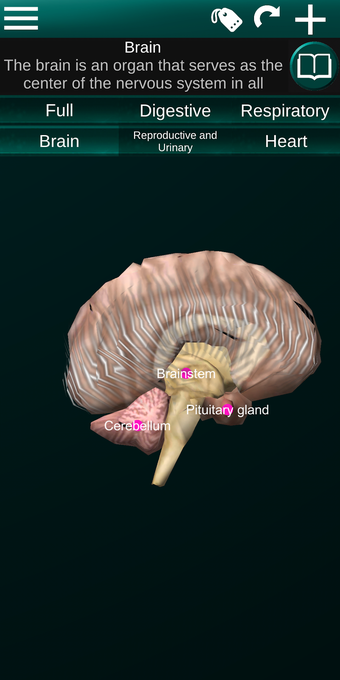

此应用程序显示人体器官的三维模型和所有器官的描述。

您可以触摸每个器官,如心脏、大脑、肺、生殖系统、肝脏、肠道、卵巢、睾丸、胃、肾脏等。

它对所有人都有用,甚至对学生也有用,因为每个解剖器官都以不同的颜色显示。